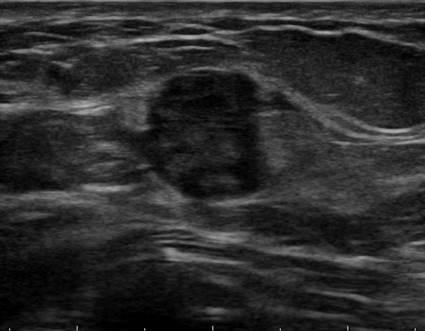

Ung thư tuyến vú

» Thông tin: Nữ giới – 45 tuổi.

» Lâm sàng: Kiểm tra sức khỏe.